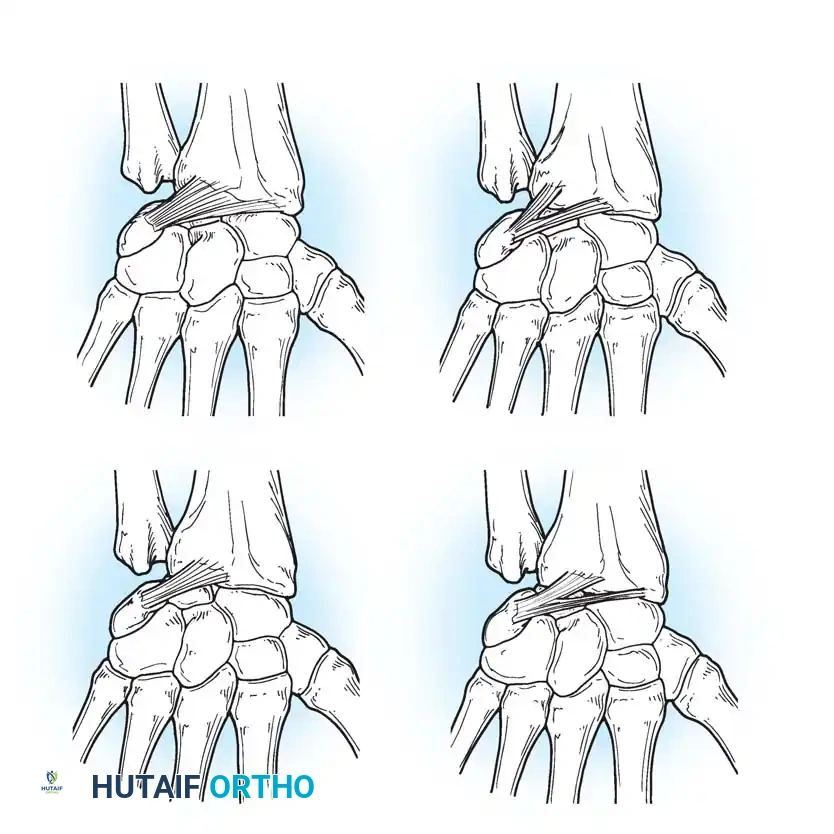

Palmar (Volar) Ligaments

The palmar ligaments are thicker and mechanically stronger than their dorsal counterparts. They are divided into extrinsic ligaments (connecting the forearm to the carpus) and intrinsic ligaments (connecting carpal bones to each other).

Key palmar extrinsic ligaments include:

* Radioscaphocapitate (RSC) Ligament: Acts as a sling supporting the scaphoid waist.

* Long Radiolunate (LRL) Ligament: Prevents ulnar translation of the lunate.

* Short Radiolunate (SRL) Ligament: Stabilizes the lunate to the lunate fossa.

* Radioscapholunate (RSL) Ligament (Ligament of Testut): Primarily a neurovascular conduit rather than a true mechanical stabilizer.

Dorsal Ligaments

The dorsal capsuloligamentous network is thinner but biomechanically vital for preventing dorsal intercalated segment instability (DISI) and guiding carpal kinematics.

The Dorsal Radiocarpal (DRC) Ligament originates from the dorsal radial margin of the lunate fossa, spans the lunotriquetral joint, and inserts onto the dorsal triquetrum. Viegas and Mizuseki classified the DRC into four distinct morphological types based on its thickness and insertion footprint.

The Dorsal Intercarpal (DIC) Ligament originates from the dorsal triquetrum, courses transversely across the midcarpal joint, and inserts onto the dorsal scaphoid waist and trapezoid. Viegas verified three distinct types of DIC ligaments, noting that its laminated structure allows it to change shape dynamically during wrist motion.

Together, the DRC and DIC form a lateral "V" shape that stabilizes the proximal row and prevents dorsal subluxation during wrist flexion.